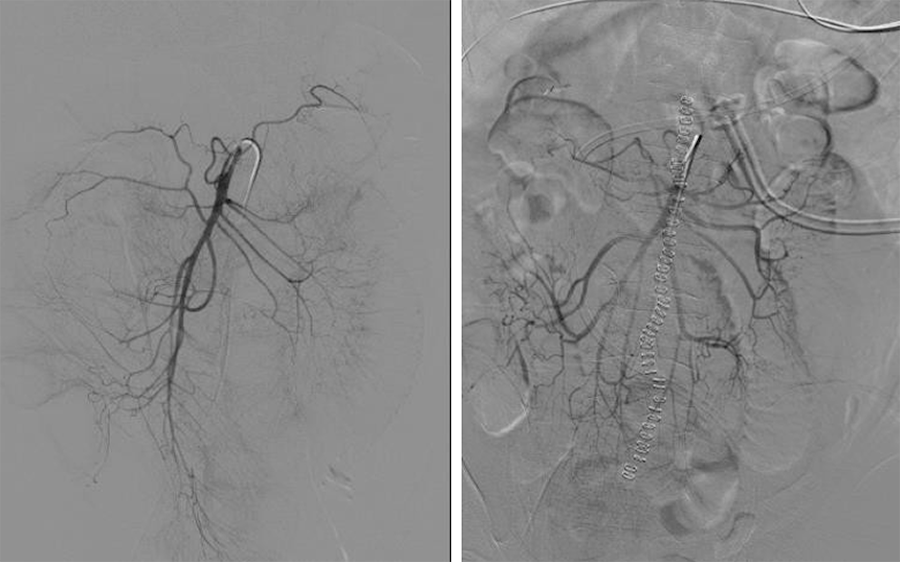

IR was consulted, and a superior mesenteric angiography showed patency of the SMA and its branches without the presence of occlusion, stenosis, or microemboli; however, the peripheral vessels appeared gracile (i.e., slender). A catheter was inserted into the superior mesenteric artery (SMA), and a Papaverine infusion was begun (Figure 3). On POD 5, he was returned to the OR for exploratory laparotomy. No evidence of intestinal necrosis was identified, and the abdomen was closed. On POD 6, the IR catheter was removed after a follow-up angiogram showed improved blood flow through the mesenteric vasculature.

Figure 3. Superior Mesenteric Angiography Before (left) and After (right) Papaverine Infusion. Published with Permission

Images show gracile (i.e., slender) peripheral vessels with improvement after IR procedure.